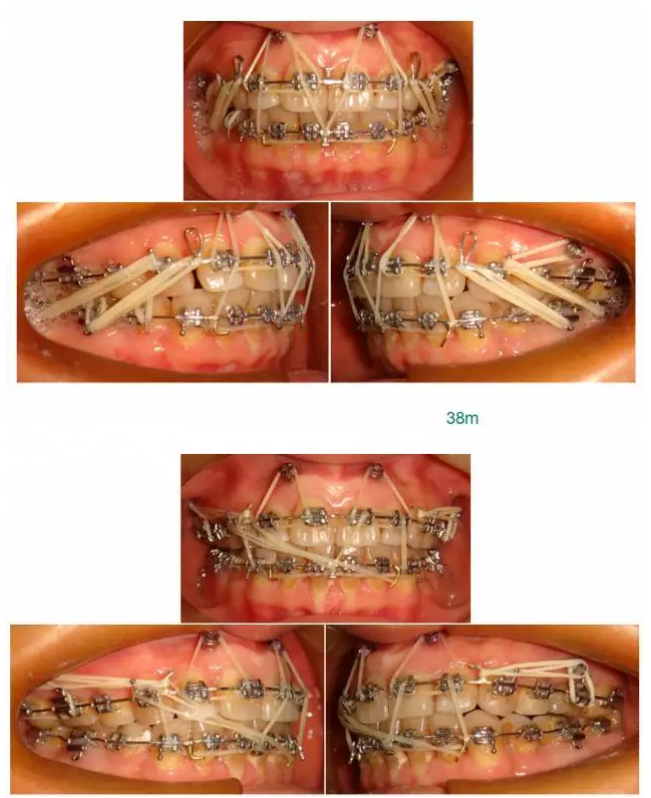

【原創(chuàng)博客】這樣的代償矯治大家滿(mǎn)意嗎?(重度骨性二類(lèi))——侯志明

轉(zhuǎn):侯志明 愛(ài)齒-KQ88口腔醫(yī)學(xué)